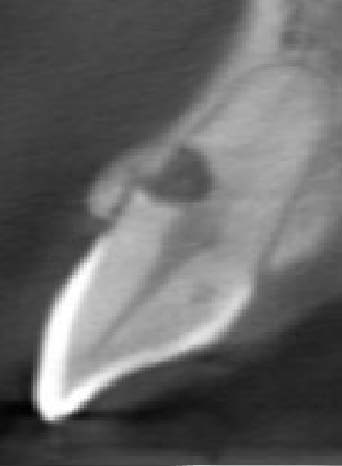

The CBCT revealed intraroot perforating resorption on the vestibular root surface. In addition, a possible cause of resorption was identified as Oehlers' Type I invagination (1957), which was based on the radiological findings. According to the classification, Type I invagination is covered with enamel and is located within the coronal part, extending no further than the enamel-dentin junction. The authors believe that the infected invagination zone with subsequent creeping infection of the root pulp brought about the resorption. The response to the cold stimulus was very insignificant, especially in comparison with tooth 12. This made it clear that an irreversible destructive process is going on in the damaged tooth. Since the patient was planning orthodontic treatment and the resorption process could grow worse, it was decided to conduct endodontic treatment.